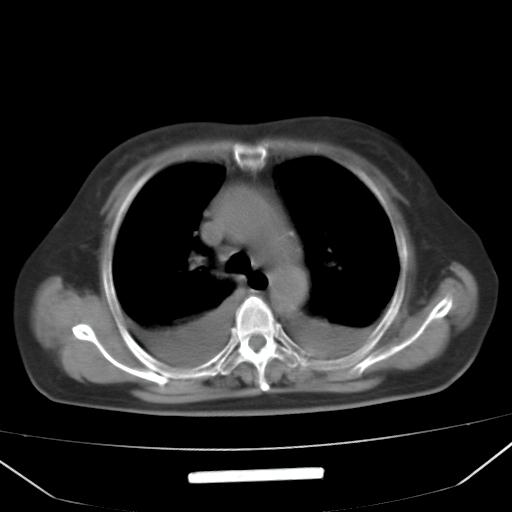

以下是引用liuyue在2008-4-19 22:25:00的发言:[br]先考虑:1.心衰伴肺水肿、双侧胸腔积液、叶间积液、双下肺不完全性肺不张; [br] 2.冠状动脉粥样硬化。

以下是引用lijuanln在2008-4-19 23:05:00的发言:[br]两侧胸腔积液,肺水肿[br]心包积液[br]提示心衰

以下是引用jiangjing在2008-4-20 10:43:00的发言:[br]结合病史支持 冠心病[冠状动脉钙化],心功能不全,肺淤血、肺水肿,双侧胸腔与斜裂积液